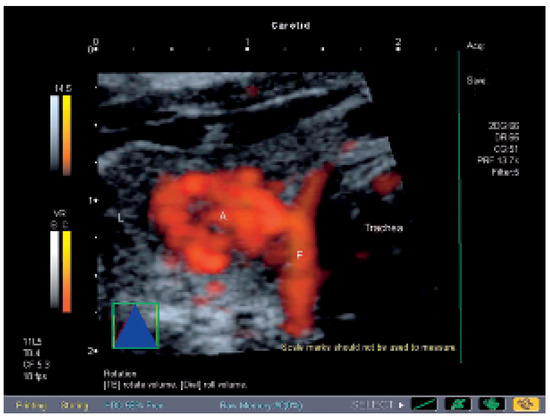

Interesting Images

Autonomes Schilddrüsenadenom und Angiosonographie

by Michel Zuber and Lukas Frey

Cardiovasc. Med. 2006, 9(10), 361; https://doi.org/10.4414/cvm.2006.01204 - 27 Oct 2006

Viewed by 59

Abstract

Eine 56jährige Patientin sucht den Hausarzt auf wegen total globaler Amnesie [...] Full article

Show Figures

Figure 1